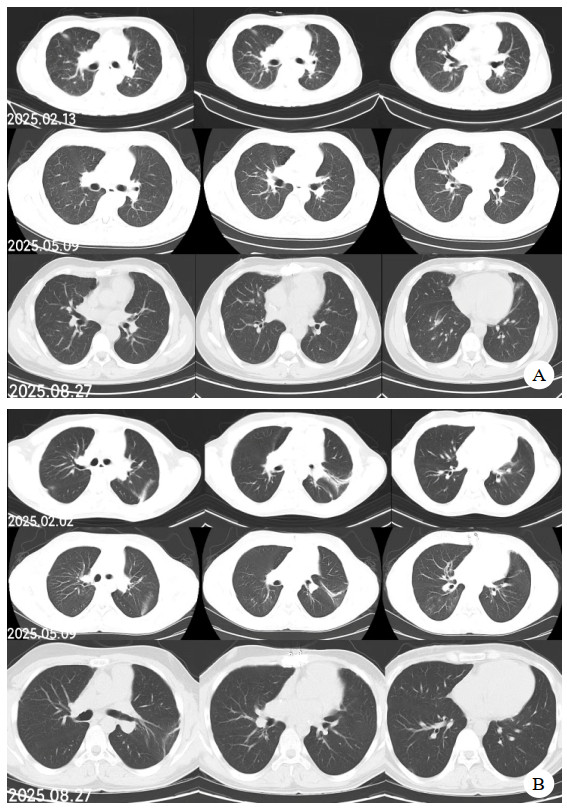

同时给予镇痛、镇静联合肌松,去甲肾上腺素泵入维持血压,俯卧位通气,B某入院后出现高热,经验性给予美罗培南联合万古霉素抗感染治疗,后降阶梯调整为哌拉西林他唑巴坦联合万古霉素治疗;C某抗感染方案为经验性使用万古霉素联合哌拉西林他唑巴坦治疗,痰培养出鲍曼不动杆菌后改为替加环素、头孢哌酮舒巴坦及万古霉素治疗;根据《刺激性气体中毒诊治专家共识》[5]中关于重症患者的治疗措施,同时给予2人泮托拉唑抑酸护胃,氨溴索、富露施化痰、甲泼尼龙抗炎、西维来司他纳及乌司他丁清除炎性介质,维生素C抗氧化、保肝、输血补液,纤支镜吸痰及肺泡灌洗,维持水电解质平衡及营养支持治疗,特别考虑到肺损伤情况,在使用有创通气时给予超保护性通气策略[5, 7];2人仍先后出现气胸、纵膈气肿,行胸腔闭式引流;持续V-V ECMO治疗15 d后,肺部纤维化不可逆转,高分辨率CT肺纤维化评分 > 75%(图 3、4),符合终末期肺病标准,有肺移植指征[8],经评估后2人顺利完成病变肺组织切除(图 5),双侧序贯肺移植,术后患者复查胸片肺部恢复正常(图 6),2位患者术后气管切管接呼吸机辅助通气,并给予泼尼松、他克莫司、吗替麦考酚酯抗排异治疗,其余根据病情给予万古霉素调节肠道菌群、抗感染、保肝、抗凝、呼吸康复锻炼等治疗,后顺利脱机、拔除气切套管,病情稳定出院,后续规律复查胸部CT(图 7)恢复良好。

| 图 3 B某发病15 d时胸部CT表现 |

| 图 4 C某发病15 d时胸部CT表现 |

| 注:图A为B某;图B为C某 图 7 肺移植术后第2个月、5个月、8个月CT影像 |